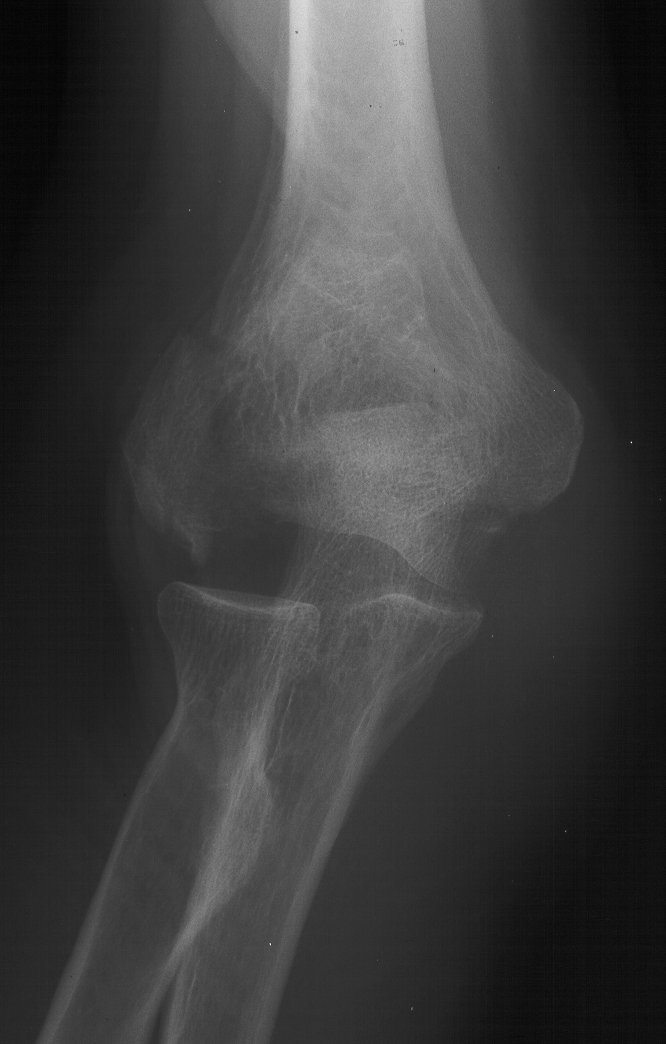

81 year old physically active woman sustained a left elbow fracture in a syncope related fall.

Lateral and central fracture component displacement.

Unusual contour visible at the medial metaphyseal flare.

This is seen on the lateral view to be the anterior half of the central articular surface.